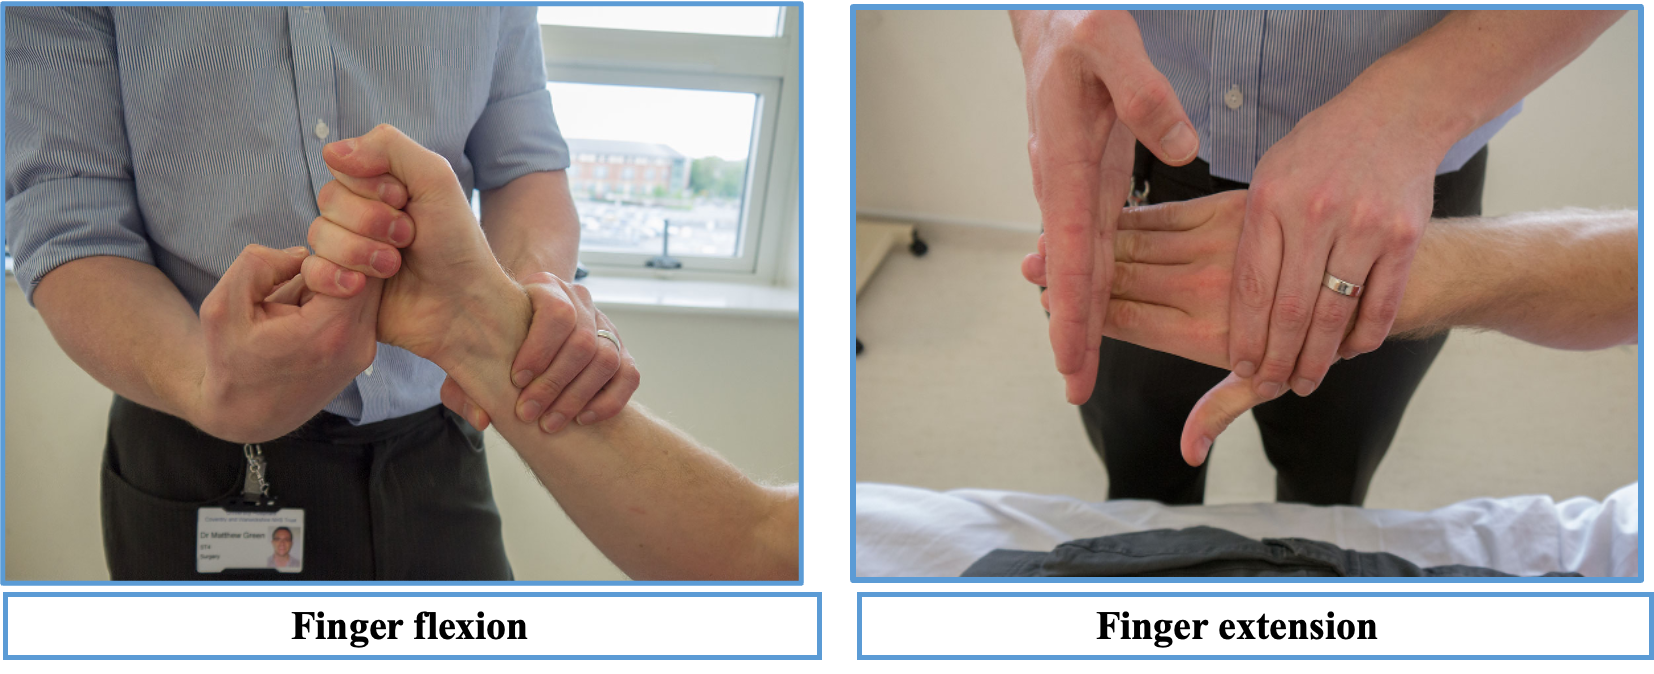

UL MOTOR EXMINATION

Power

Start at the shoulder asking the patient to abduct and adduct against your hand so you can assess how much force they can overcome. Do the same for flexion and extension at the elbow and wrist, as well as the fingers; also checking abduction and adduction of the thumb.